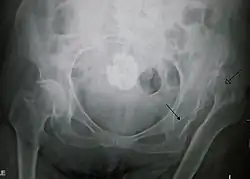

An anterior-posterior (AP) X-ray of the pelvis and a cross-table lateral X-ray[24] of the effected hip are ordered for diagnosis.[4][5][16] The size of the head of the femur is then compared across both sides of the pelvis. The affected femoral head will appear larger if the dislocation is anterior, and smaller if posterior.[7] A CT scan may also be ordered to clarify the fracture pattern.[20]

Nonoperative

The hip should be reduced as quickly as possible to reduce the risk of osteonecrosis of the femoral head.[4] This is done through manual traction of the thigh inline with the dislocation under general anesthesia and muscle relaxation, or conscious sedation.[4][7] Fractures of the femoral head and other loose bodies should be determined prior to reduction. Of note, femoral neck fractures, femoral head fractures, and incarcerated fracture fragments preventing joint reduction are contraindications.[25][5][26] Common closed reduction methods include the Allis method, Stimson Gravity Technique, and the Bigelow maneuvers.[4][27] Once reduction is completed, management becomes less urgent and appropriate workup including CT scanning can be completed.[7]